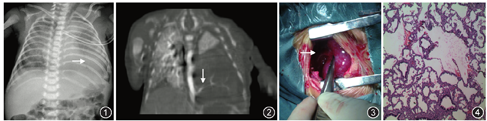

入院诊断:早产儿胸腔积液。入院后辅助检查:血常规:WBC 16.44×109/L,N 49.2%,L 33%,血红蛋白144 g/L,血小板407×109/L,CRP<1 mg/L。胸水常规:细胞数260×106/L,单核细胞85%,李凡它试验阴性,乳糜试验阴性,胸水生化:总蛋白9.2 g/L,腺苷脱氨酶1.5 U/L,乳酸脱氢酶49 U/L,葡萄糖5.19 mmol/L。血生化:总蛋白49.9 g/L,白蛋白35.3 g/L,球蛋白14.6 g/L,谷丙转氨酶7 U/L,肌酐63.4 μmol/L,尿素7.31 mmol/L,乳酸脱氢酶298 U/L,肌酸激酶89 U/L,CKMB 24 U/L。胸水培养、血TORCH及微小病毒B19检测阴性,心超提示心脏结构及功能正常,甲状腺功能、染色体核型、遗传代谢病筛查结果均正常。胸腔B超:左侧胸腔积液,左侧胸腔内强回声,实变肺组织可能。胸片(图1)示:左侧少量气胸,左下肺透亮度减低,考虑胸腔积液,同时可见片状密度增高影。入院后第5天胸部CT示:左下肺大片状密度增高影,纵隔右移,第7天螺旋CT增强扫描(图2):左下胸腔大片软组织密度影似有不规则少量轻度强化,并见从降主动脉右膈顶水平处发出一支血管进入该肿块。患儿入院后予以呼吸机支持,抗感染,胸腔闭式引流等对症支持治疗,每日引流量约40~50 ml。入院后第11天胸外科予以手术,术中见左侧胸腔内大量淡黄色液体,左侧胸腔下侧见一孤立的组织,大小5.5 cm×4 cm×3 cm,外观暗红色有包膜,与正常左肺组织无连接,根部可见血管蒂(图3)。切除组织病理(图4):部分肺不张及肺气肿,支气管淋巴组织增生,肺泡腔少量炎症细胞浸润,未见明显囊肿形成。术后诊断:左侧叶外型肺隔离症伴胸腔积液。患儿术后第3天顺利撤离呼吸机,术后第1天胸腔引流液20 ml,第3天未见引流液出现,第5天拔除胸腔引流管,治愈出院。

由于隔离肺与支气管多不相通,故病肺内分泌物无法排出而易形成囊肿,并易继发感染;一旦隔离的肺组织与支气管相通,继发感染使其形成较大的液气腔或脓腔。所以目前认为肺隔离症一旦诊断明确,应该积极手术治疗。对于有症状的患儿手术时机取决于呼吸窘迫严重程度和肺部感染情况,需在感染消退后择期手术切除病肺。对无症状的叶内型肺隔离症多数学者主张预防性手术切除,特别是影像学上与囊性病变及肿瘤难以区分时。本例持续呼吸困难伴胸腔积液,术前影像学诊断考虑肺隔离症,因而采取手术方案。术中见左侧胸腔内大量淡黄色液体,左侧胸腔下部见一孤立组织,大小5.5 cm×4 cm×3 cm,外观暗红色有包膜,与正常左肺组织无连接,根部可见血管蒂。经切除组织病理检查显示病变组织有肺泡、支气管等呼吸上皮结构,未见明显囊肿形成。最终手术证实患儿诊断为左侧叶外型隔离肺伴胸腔积液。新生儿并非手术禁忌人群,国外已有数十年经验证实新生儿肺隔离症手术治疗的安全性和良好的长期预后。国内虽然有胎儿及新生儿肺隔离症的报道,但尚无手术先例,本例为国内首例成功手术治疗的新生儿肺隔离症,为今后类似病例积累了经验。